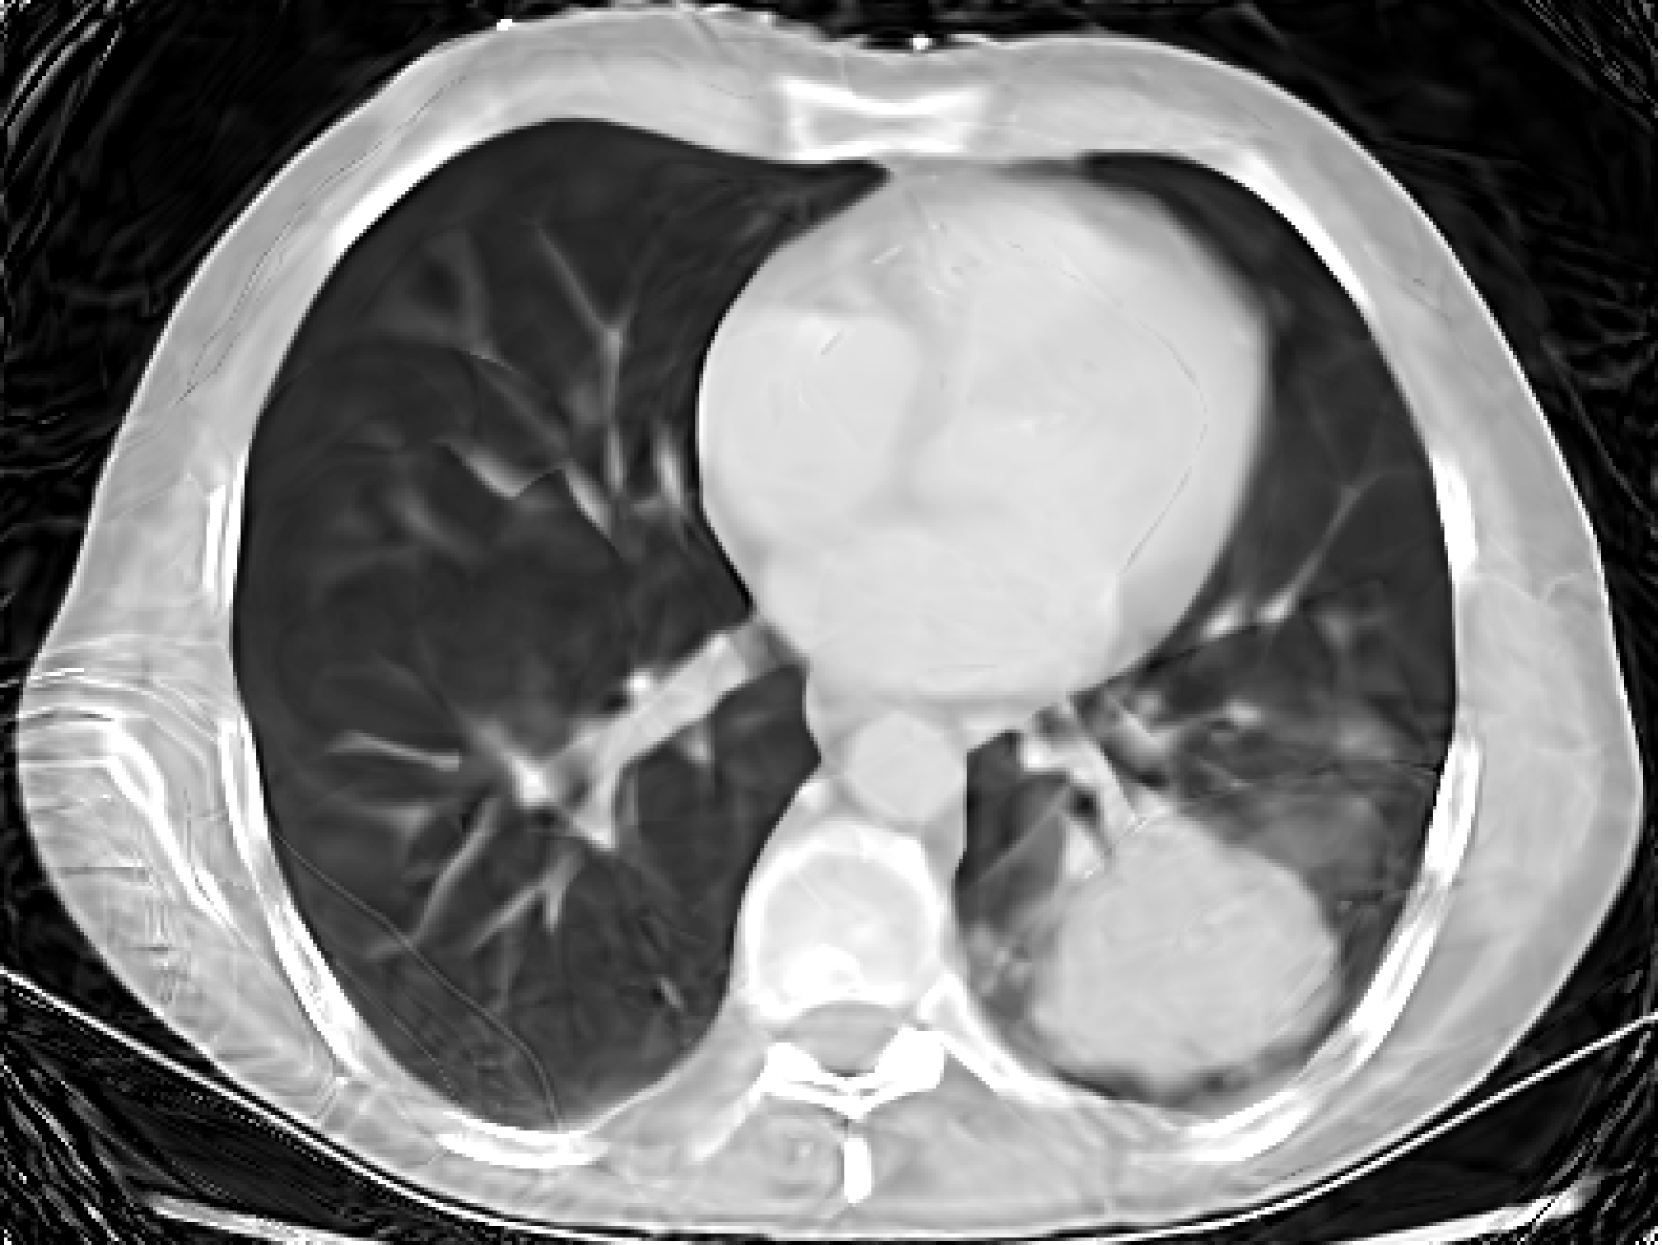

Figure 4: Experiments on computed tomography reconstruction with various INR architectures. We report average PSNR and standard error across five random trials.

5.1 Computed Tomography(CT) Reconstruction

In this experiment we simulated CT reconstruction by taking 100100100100 equally spaced CT measurements of a 326×435326435326\times 435326 × 435 chest X-ray image (Clark et al., 2013). Figure 4 shows the results compared to other INR architectures showing that our BW-ReLU neural networks perform just as well and perhaps slightly better than conventional INR architectures. Full experiment details can be found in Section D.1.